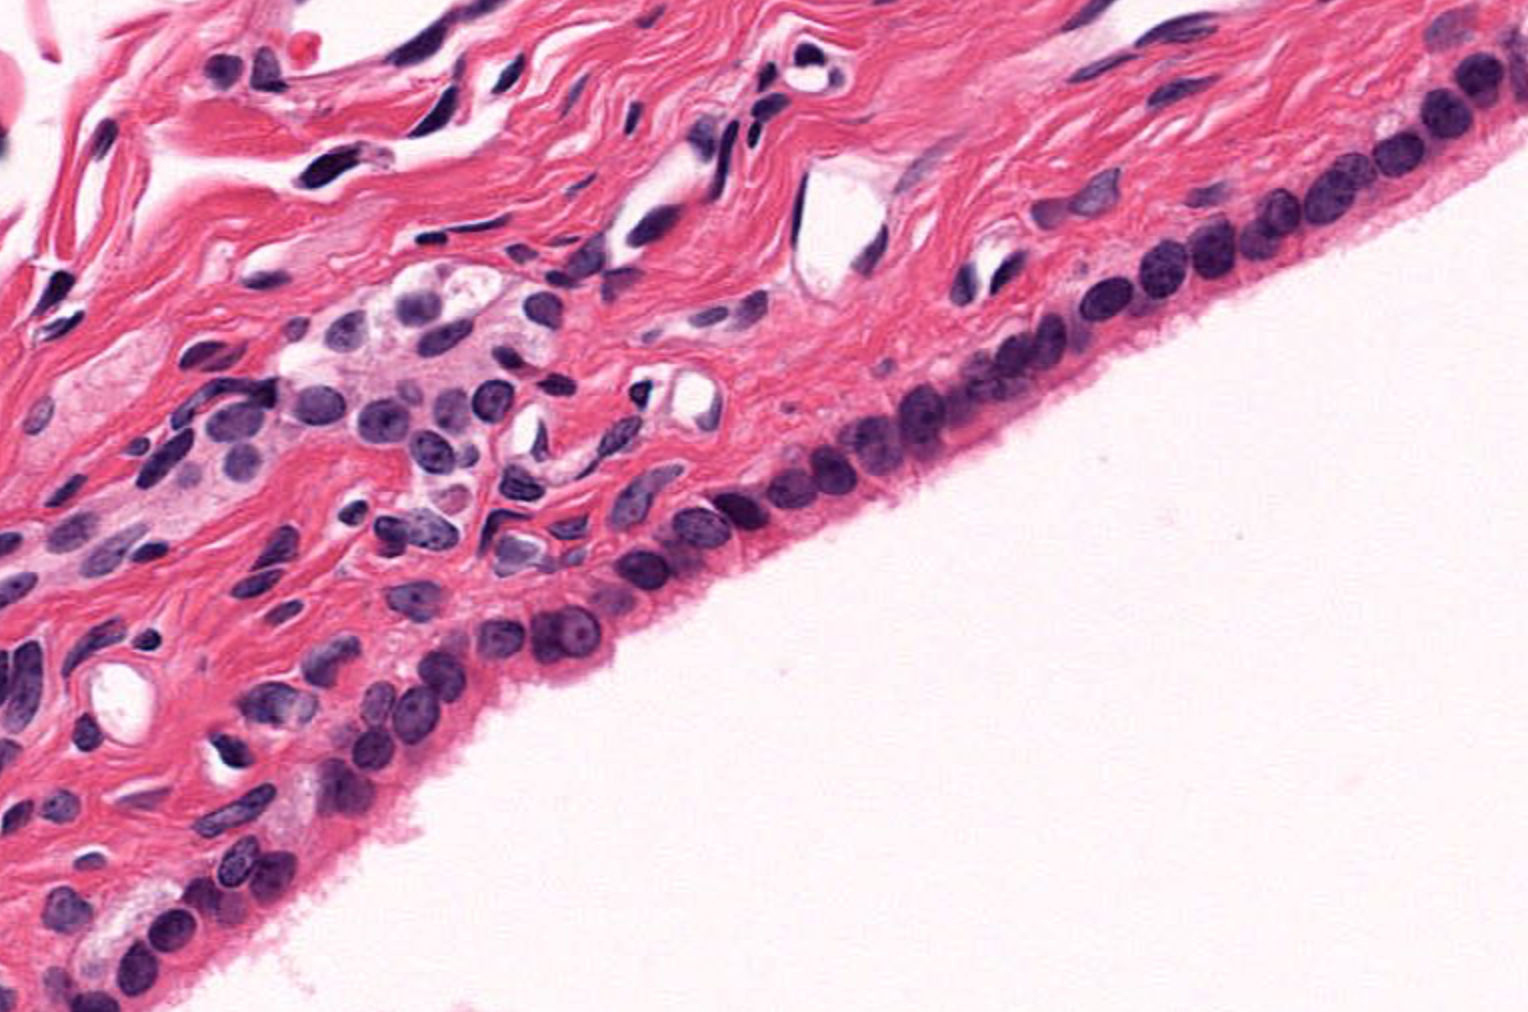

term image

Tissue: simple squamous epithelium

Location:

• kidneys

• alveoli

• lining of heart, blood and lymphatic vessels

• ventral body cavity lining

Function:

• diffusion and filtration

• secretes lubricating substance